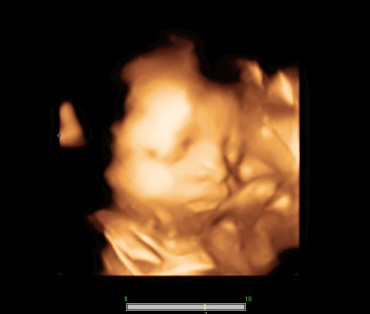

หนูเป็นผู้หญิงค่ะ 31weeksแล้วค่ะ

ซาวแบบนี้เรียกซาวรัยคะ ราคา

ตอน 27 +2 วันจ้า เพศชายจ้า😍😍